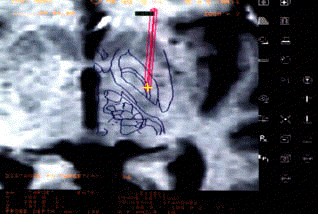

The development of radiosurgery by a Swedish neurosurgeon, Dr. Lars Leksell, in the 70s, now allows physicians to remove tiny amounts of brain tissue without actually opening the skull. Using directed beams of high-energy radiation produced by a linear accelerator, a nuclear pile or external sources of radioactive cobalt, as well as computers and advanced neural imaging techniques (computed tomography), surgeons are now able to pinpoint with great accuracy areas, nuclei or fibers inside the brain. However, fewer than 200 surgeries of this type were performed every year in the United States, because its indication is highly selective.